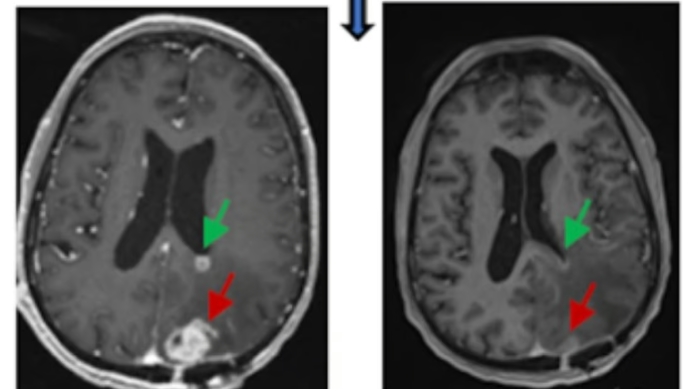

CAR T 치료법은 암세포에서 발견되는 특정 단백질을 찾아 파괴하도록 재 프로그래밍된 환자의 면역체계 T세포의 힘을 활용하는 방식이다. 치명적인 교모세포종(GBM) 환자에 초점을 맞춘 새로운 시험에서 CAR T는 두 가지 단백질 표적에 초점을 맞춰 종양 세포가 숨을 수 있는 공간을 훨씬 더 적게 제공했다는 것이다. 실제 시험에 등록한 6명의 환자 모두의 MRI 뇌 스캔 결과, 치료 후 하루나 이틀 이내에 종양이 빠르게 감소하는 것으로 나타났다. 펜실베니아대학 UPenn 연구소 혈액종양학 및 신경외과 Donald O' 박사는 “어떤 경우에는 이러한 감소가 몇 달 동안 계속되었다”면서 "이중 표적 CAR T 세포 치료법이 재발성 GBM을 앓고 있는 더 넓은 범위의 개인에게 어떻게 영향을 미치는지 더 폭넓은 시험을 계속할 것"이라고 밝혔다. 교모세포종은 성인 뇌종양의 가장 흔하고 가장 공격적인 형태로, 진단 후 예상 수명은 12~18개월에 불과하다. 또한 수술, 방사선, 화학 요법 등의 특정 치료법으로 잠시 동안 종양을 퇴치할 수 있지만 재발이 흔하며, 재발 후 일반적으로 1년 이내에 사망한다. 연구팀은 CAR T 치료법은 혈액 악성 종양과 싸우기 위해 오랫동안 성공적으로 사용되어 왔지만 고형 종양은 훨씬 더 어려운 표적이었다고 연구 배경을 설명했다. 수석 연구원인 Stephen Bagley 박사는 "GBM 및 기타 고형 종양의 문제는 종양 이질성이다. 즉, GBM 종양 내의 모든 세포가 동일하거나 CAR T 세포가 공격하도록 조작된 동일한 항원을 갖지 않는다는 의미이다."면서 "모든 사람의 GBM은 저마다 다르기 때문에 한 환자에게 효과가 있는 치료법이 다른 환자에게는 효과적이지 않을 수도 있다."고 덧붙였다. “교모세포종은 면역계 세포, 심지어 CAR T에 사용되는 재 프로그램된 세포를 회피하는 데에도 능숙하다. 향후 과제는 종양 방어를 중심으로 치료를 통해 종양을 죽일 수 있도록 하는 것"이라고 강조했다. 새로운 실험에서 연구팀은 종양 세포에 있는 두 가지 단백질 을 표적으로 삼아 종양의 탈출 가능성을 제한하기로 결정했다. 연구팀은 “표피 성장인자 수용체(EGFR)는 모든 교모세포종의 60%에 존재하는 것으로 생각된다. 그리고 이 종양의 75% 이상에서 발견되는 인터루킨-13 수용체 알파 2(IL13Rα2)가 있다. CAR T 세포가 뇌로 직접 이동하도록 하는 방법을 만들었다. 평소처럼 IV 드립을 통해 전달하는 대신 팀은 이를 각 환자의 척수액에 주입하여 뇌로 직접 이동했다.”고 연구과정을 설명했다. “그 결과 이 전략은 효과가 있는 것처럼 보였다. CAR T 전달 후 불과 24시간과 48시간 만에 촬영한 MRI 스캔에서 종양이 눈에 띄게 줄어드는 것으로 나타났다. 이러한 감소는 일부 환자에서 몇 달 후에도 지속되었다."라고 밝혔다. 연구팀은 “물론 모든 치료법에는 부작용이 있을 수 있으며, CAR T는 건강한 뇌 세포도 죽일 수 있다. 이를 신경독성이라고 한다. 그러나 상당한 수준의 신경독성이 발생했지만 환자는 이를 관리할 수 있었다.”고 말했다. O'Rourke 박사는 “치료의 성공을 확인하고 최적화하기 위해서는 더 많은 연구가 필요하다."면서도 ”이 암은 각 개인마다 고유하므로 더 넓은 범위의 환자가 최적의 복용량을 결정하고, 신경 독성과 같은 효과를 더 잘 이해하며, 효능을 더욱 확고히 확립하는 데 도움이 될 것"이라고 강조했다. 이번 연구 결과는 Nature Medicine 저널 최근호에 게재되었다. | |||||||||